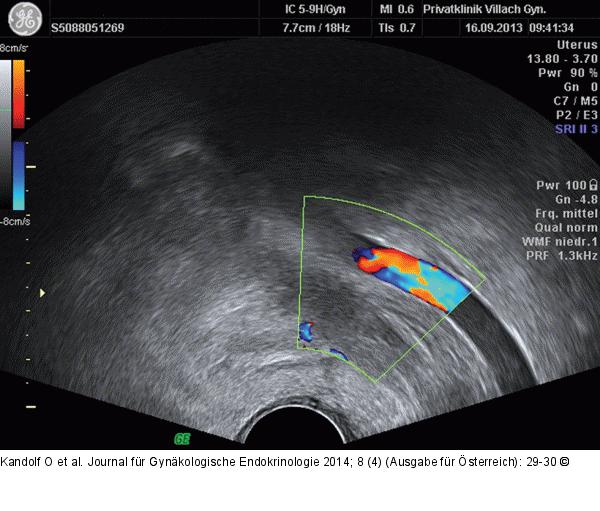

Abbildung 2: Venöse Thromboembolie Vaginalsonographie li. Beckenwand: A. iliaca li. mit thrombosierter Vene bei der Aufnahme. |

Abbildung 2: Venöse Thromboembolie

Vaginalsonographie li. Beckenwand: A. iliaca li. mit thrombosierter Vene bei der Aufnahme. |